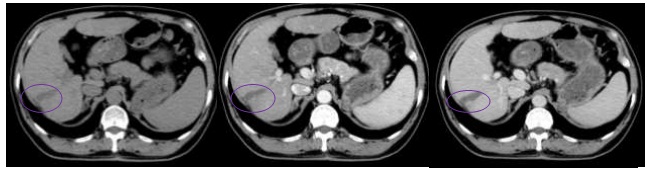

Hình 6: Hình ảnh CT bụng sau 9 tháng: Vùng giảm tỷ trọng hạ phân thùy VI, kích thước 2,6×3,2 cm, không ngấm thuốc (vòng tròn vàng)

Hình 7: Hình ảnh CT bụng tháng sau 12 tháng: Vùng giảm tỷ trọng hạ phân thùy VI, KT 3,1×1,0cm, không ngấm thuốc, co kéo bờ gan (vòng tròn xanh nhạt)

Nhận xét: Trước điều trị khối u ngấm thuốc điển hình của HCC (hình 5), tuy nhiên sau điều trị ở thời điểm 9 tháng trở đi khối u giảm về kích thước, không ngấm thuốc sau tiêm nên đạt được bệnh đáp ứng hoàn toàn theo tiêu chuẩn mRECIST (hình 6,7,8,9).